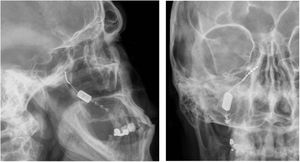

Neuromodulación del ganglio esfenopalatino ipsilateralLas experiencias iniciales de estimulación del ganglio esfenopalatino (GEFP) ipsilateral al dolor en la cefalea en racimos (CR) con electrodos no implantados17,67, mostraron eficacia en un 61% de pacientes. Posteriormente, se diseñó un microestimulador implantable en el GEFP que se coloca previo análisis radiológico de la fosa pterigopalatina con tomografía axial computerizada68 y profilaxis antibiótica. El abordaje es transoral utilizando una incisión gingival mínimamente invasiva69 con anestesia general e ingreso de 24 horas. Puede utilizarse navegación70 y, finalmente, se realiza una radiografía simple para verificar su posicionamiento (fig. 4).

El estimulador se activa mediante un mando inalámbrico que se aproxima a la mejilla y en el que esta insertada la batería, por lo que no se requiere cableado, ni generador subcutáneo, ni recambios quirúrgicos de baterías.